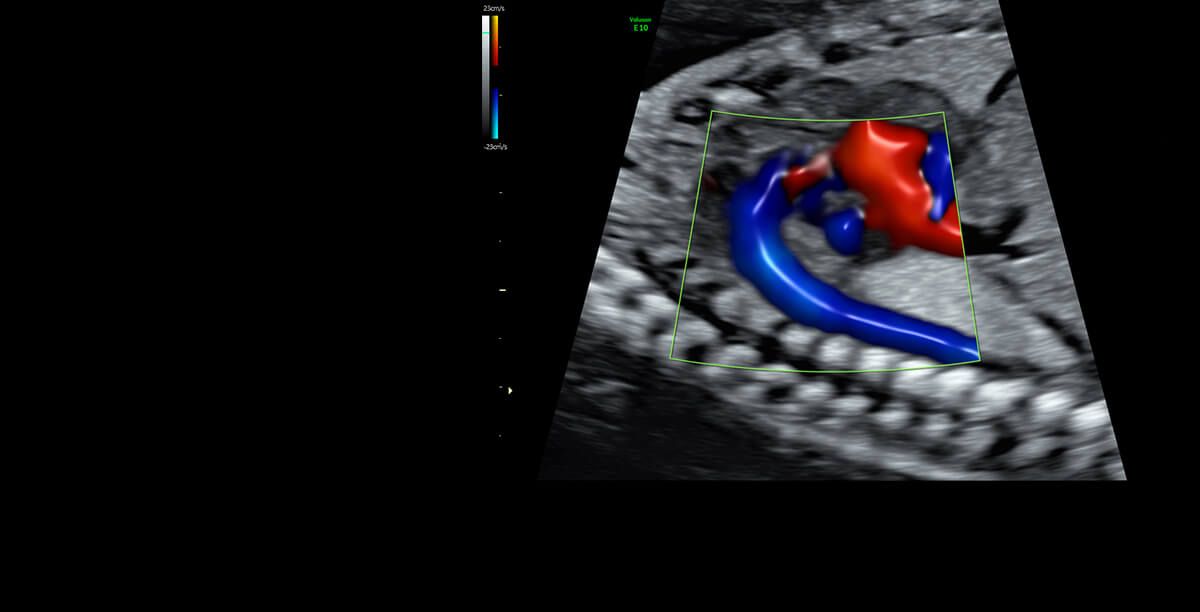

Jestem lekarzem, ginekologiem-położnikiem, absolwentką Collegium Medicum Uniwersytetu Jagiellońskiego w Krakowie. Przez długi czas byłam związana z Katedrą Ginekologii i Położnictwa Uniwersytetu Jagiellońskiego Collegium Medicum w Krakowie jako nauczyciel akademicki. W 2007 roku uzyskałam nostryfikację dyplomu lekarskiego w Stanach Zjednoczonych. Tytuł doktora nauk medycznych uzyskałam na podstawie obronionej rozprawy doktorskiej z zakresu problematyki układu immunologicznego w ciąży pozamacicznej. Praca lekarza jest moją wielką pasją, a moje doświadczenie kliniczne zdobyłam pracując w Oddziale Ginekologii i Onkologii Szpitala Uniwersyteckiego w Krakowie. Jestem doświadczonym specjalistą w zakresie ultrasonografii położniczej, ginekologicznej i onkoginekologicznej, a wszystkie badania wykonuję zgodnie z najnowszymi rekomendacjami Sekcji Ultrasonografii Polskiego Towarzystwa Ginekologicznego, Fetal Medicine Foundation (FMF) oraz The International Society of Ultrasound in Obstetrics and Gynecology (ISUOG). Moje zainteresowania dotyczą również zagadnień dotyczących diagnostyki i leczenia niepłodności oraz metod wspomaganego rozrodu. W trosce o najlepszą opiekę nad Pacjentkami staram się poszerzać moją wiedzę przez uczestnictwo w licznych kursach i kongresach. Będąc lekarzem, a zarazem kobietą mam świadomość jak intymnym przeżyciem jest wizyta u ginekologa, dlatego zwracam uwagę na indywidualne podejście do każdej Pacjentki, tak jak sama chciałabym być leczona będąc Pacjentką.

I am a physician, a gynecologist- obstetrician. I graduated from the Jagiellonian University Medical College. For a long time, I worked as a university teacher at the Department of Gynecology and Obstetrics, Jagiellonian University Medical College. In 2007, my medical doctor’s diploma, which I received in the USA, was officially recognized. My MD-PhD I obtained on the basis of my doctor thesis dealing with the problems concerning the immune system in the ectopic pregnancy. This profession is my passion. I gained my experience working at the Department of Gynecology and Oncology in the Krakow University Hospital. I am an experienced specialist in obstetric, gynecologic and oncologic ultrasound, and all of my examinations are carried out according to the newest recommendations of the Ultrasound Section of the Polish Gynecological Society, Fetal Medicine Foundation (FMF) as well as The International Society of Ultrasound in Obstetrics and Gynecology (ISUOG). My interests also include issues concerning the diagnosis and treatment of infertility and methods of assisted reproduction. Out of concern for my Patients, I constantly try to extend my knowledge through participating in numerous courses and congresses. Being both a doctor and a woman, I am aware of the intimacy of an appointment at a gynecologist, and that is the reason why I pay a special attention to an individual approach to each of my Patients, which is the way I would like to be treated as a Patient. Best regards, Anna Knafel